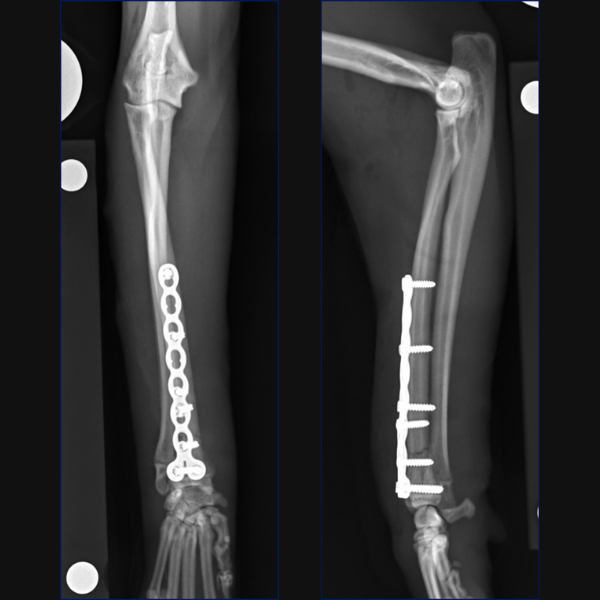

For this case, as anatomic reduction was possible, an open approach was elected with stabilization of the radius being achieved through a craniolateral approach and use of a 1.5/2.0 notched T-plate. 3 locking screws were placed distal to the fracture site with 2 locking and 2 non-locking screws being used proximally. Compression was attempted, but you can see that a small gap remains on the transcortex, so I could have pre-stressed my plate a little better.

Reduction of the radial fracture completely reduced the ulnocarpal luxation. We assessed for instability intraoperatively using the same technique which is reported in people which involves stabilizing the radiocarpal joint with one hand and then trying to move the ulna independently in a dorsal and palmar direction. Based on our assessment, no instability was palpable and as such, no distal radioulnar fixation was considered necessary.